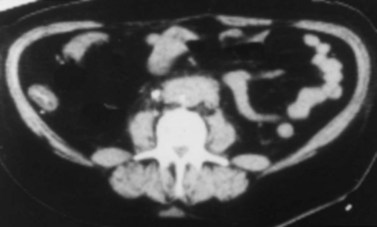

In most RPF patients, the clinical symptoms are generally nonspecific, and physical examination is usually unrevealing. Laboratory evaluation may reveal an elevated erythrocyte sedimentation rate, moderate leukocytosis, anemia, and variable renal insufficiency with associated electrolyte abnormalities. If the overall renal function is normal, an excretory urogram (EVU) or more commonly computed tomography (CT) with contrast may be performed. Typical EVU findings include hydronephrosis with medial deviation of the proximal ureter and midureter and a smoothly tapered ureter at the level of obstruction. Urinary obstruction is usually bilateral, but unilateral cases have been described. Uncommonly, there are patients with symptoms of urinary obstruction but little hydronephrosis on imaging. CT scan typically reveals hydronephrosis associated with a well-delineated retroperitoneal soft tissue mass enveloping the great vessels and the ureters (Fig. 41–36). If the patient has significant renal impairment, a retrograde pyelogram may be performed. In the radiographic evaluation of RPF, magnetic resonance imaging (MRI) can also be helpful because the mass itself has characteristic T1- and T2-weighted images. Retroperitoneal fibrosis is characterized as a diffusely low signal intensity on T1-weighted imaging, although the T2 signal may vary considerably, with high signal intensity consistent with active disease (Fig. 41–37A and B). With treatment, T2 signal often diminishes and thus provides a measure of therapeutic efficacy. Moreover, gadolinium enhancement may also prove valuable in assessing the response to treatment because associated decreases in gadolinium contrast enhancement should also be expected following appropriate therapy (Cronin et al, 2008). If a kidney is suspected to be nonfunctioning, differential renography should be considered to determine renal function because it may affect surgical planning. Representative biopsies of the mass should be obtained percutaneously or at the time of open or laparoscopic ureterolysis to rule out malignancy and allow one to proceed with treatment for RPF.